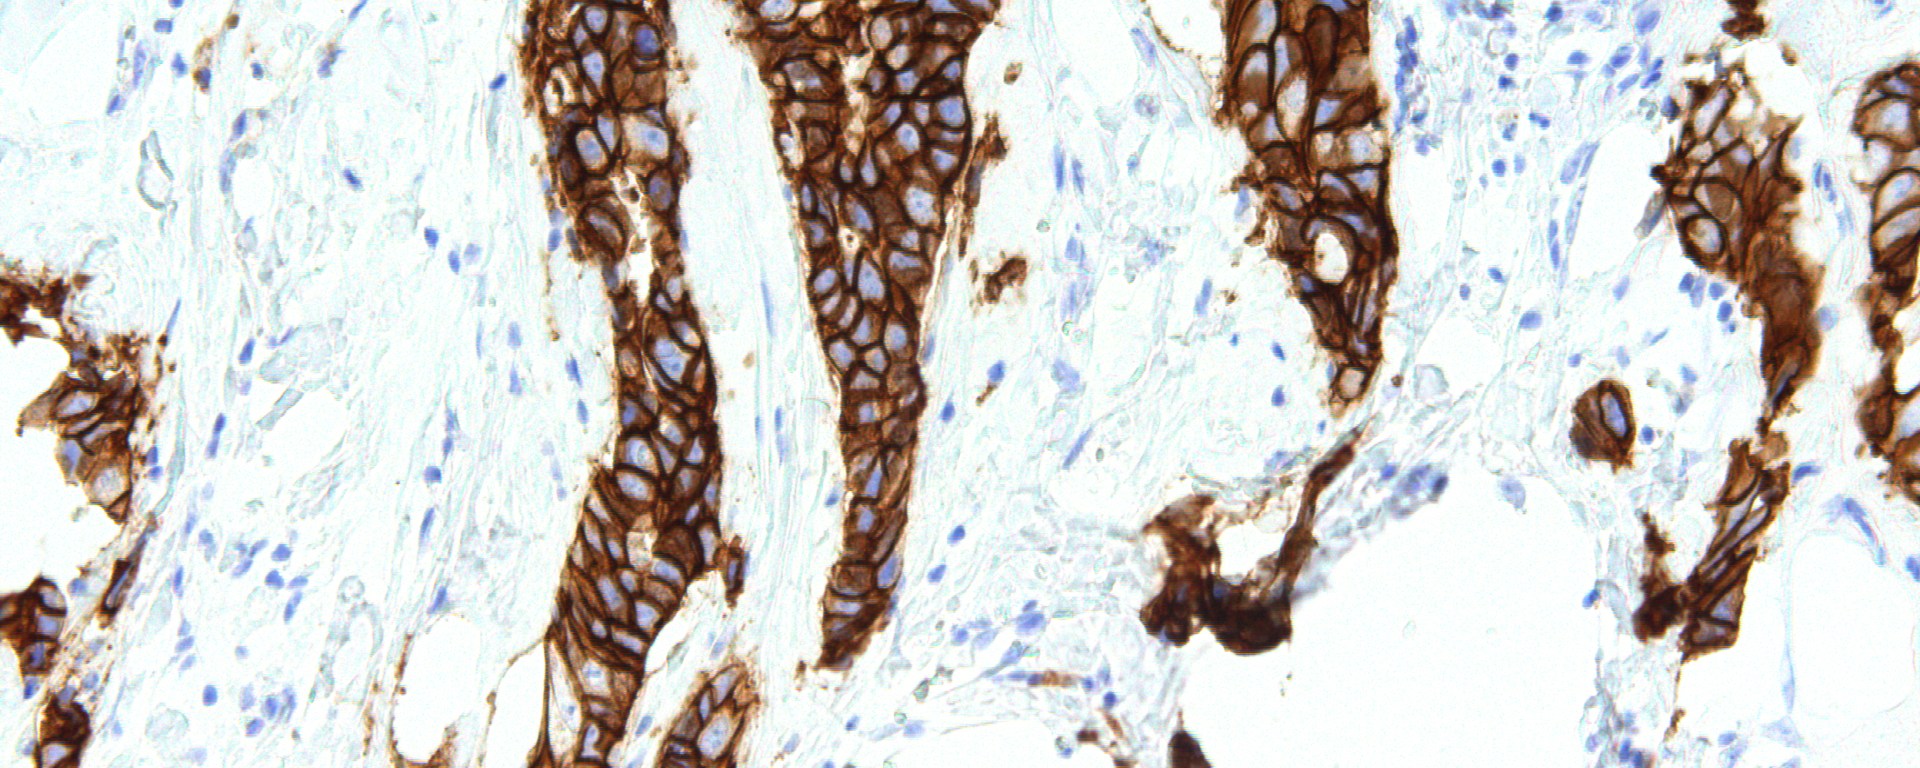

Figure 1. HER2 is a protein that has been strongly implicated in many human cancers, particularly breast cancer, and has been demonstrated to induce carcinogenesis through a variety of different mechanisms. This breast cancer tissue has been stained for HER2.

Some of the latest research by Stephen J. Collins of the Miller lab, a part of Stony Brook University’s Department of Physiology & Biophysics, provides key insights into the mechanism behind the development of human cancers and some alternative treatments to what is currently being offered to patients. Their research focused on human epidermal growth factor receptor 2 (HER2), which is a receptor tyrosine kinase that has been previously identified as a prominent oncogene in many human cancers (primarily in breast cancer) making it an important therapeutic target. In HER2-positive breast cancers, HER2 is sometimes mutated, often leading to its constitutive activation causing increased activation of downstream pathways, several of which have also been implicated in carcinogenesis. The goals of their research were as follows: to characterize the effects of two activating mutations in HER2 and identify compounds capable of inhibiting these HER2 mutants.